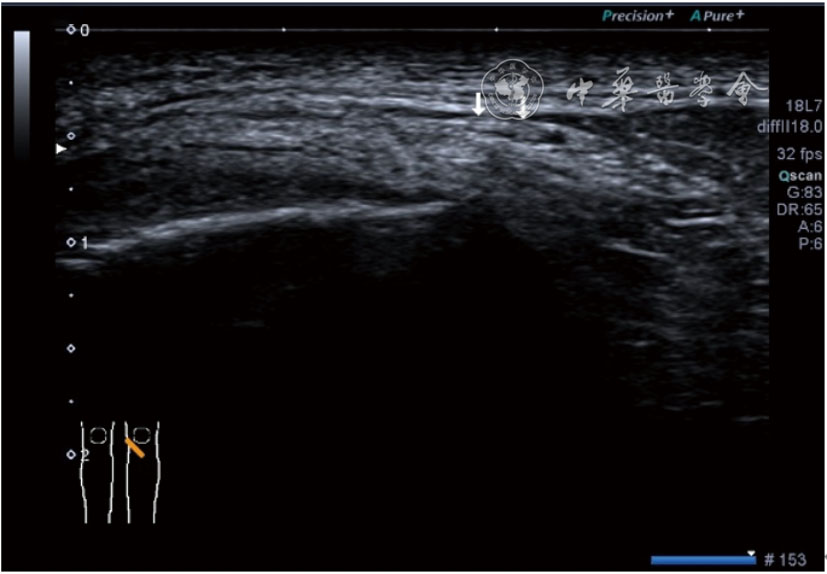

图19 超声引导下髌上囊积液抽吸加臭氧注射治疗

3.膝关节内局部治疗。随着病情发展,静态结构失衡,膝关节内部结构发生变化,会出现软骨损伤、脱落,关节间隙变窄,内外间隙不等,骨赘形成等。膝关节内局部治疗包括关节内症状性骨赘剥离、玻璃酸钠及PRP注射等。(1)膝关节内症状性骨赘针刀剥离松解治疗。由于软骨缺损或者力平衡失调,在关节内脱落软骨区会出现骨赘。部分骨赘引起疼痛,或者与髌骨撞击出现临床症状需要治疗。针刀剥离目的不是去除骨赘,而是剥离松解,缓解或者消除疼痛。以股骨外髁骨赘为例。患者平卧位,膝关节屈曲100°~120°。一般选用10 MHz超声探头,穿刺区域常规消毒,探头涂抹耦合剂后套入无菌手套碘伏消毒或使用无菌耦合剂。将探头置于患者皮肤表面,短轴扫查,显示关节面与骨赘,选用25G注射针,抽吸1%利多卡因3 ml于骨赘周围进行分层麻醉。选用直径1 mm的Ⅰ型2号针刀,在超声引导下从外侧向内侧到达骨赘,反复剥离,一般5~8刀后拔出针刀结束治疗(图18),局部压迫5分钟,无菌敷料覆盖。(2)膝关节髌上囊积液治疗。髌上囊积液在膝关节骨关节炎比较常见,尽管积液量可能很大,但通过软组织松解治疗后,大部分患者积液会减少或者消失。所以积液的治疗可以放在后面处理。超声引导下抽出积液,药物注射是常用的治疗方法。膝关节炎积液的治疗通常包括关节内皮质类固醇激素或者臭氧注射。如果慢性以滑膜丛型增生为主,针刀有限切割增生滑膜加药物注射可提高疗效。①髌上囊积液抽吸加臭氧注射治疗。患者平卧位,膝关节屈曲30°~60°,膝下垫一软枕。选用10 MHz超声探头,治疗前消毒准备同骨赘针刀剥离松解治疗。将探头置于患者皮肤表面,短轴扫查,找到积液最多处,应用22G针头,直接穿刺进入髌上囊抽出液体,然后根据髌上囊大小制备35 μg/L的15~20 ml臭氧注入髌上囊内拔出针头(图19),局部压迫2分钟,无菌敷料覆盖。②髌上囊慢性滑膜炎针刀切割松解治疗。患者平卧位,膝关节屈曲30°~60°,膝下垫一软枕。选用10 MHz超声探头,治疗前消毒准备同骨赘针刀剥离松解治疗。将探头置于患者皮肤表面,长轴或短轴扫查,找到积液最多处,用一次性5 ml注射器抽吸1%利多卡因3 ml于髌上囊进行分层注射麻醉,囊内也要注射适量麻药,尽量抽出积液。选用直径1 mm的Ⅰ型2号针刀,长轴扫查从近端向远端,短轴扫查从外侧向内侧,在超声引导下进入囊肿内对内壁及增生滑膜的不同方向、角度进行反复切割(图20),一般2~3分钟拔出针刀,然后囊内注射1%利多卡因3 ml+曲安奈德15 mg,结束治疗,局部压迫5分钟,无菌敷料覆盖。(3)膝关节腔PRP注射治疗。关节腔注射主要是为了修复软骨,如果不是为了治疗积液,不主张应用激素类药物。目前主要的注射药物为玻璃酸钠、PRP。按照传统的注射部位,多为髌上内、外或者髌下内、外注射点,但是超声不能观察到注射针的位置,药物也不能很好到达软骨损伤的部位,效果受到影响(图21)。膝关节软骨损伤的主要部位在髌股关节的股骨髁,超声可以很好地显示这一部位,并能显示软骨变薄。因此,由这个路径平面内进针注射,可以很好显示穿刺针的路径与位置。以注射PRP为例。患者平卧位,膝关节屈曲100°~120°,选用10 MHz超声探头,治疗前消毒准备同骨赘针刀剥离松解治疗。将探头置于患者皮肤表面,短轴扫查显示关节面,应用25G注射针头,抽吸1%利多卡因2 ml由内侧进针进行分层麻醉直达关节软骨面。制备4.5 ml PRP,直接注射到关节面,液体顺关节面分布,注射完毕拔出针头(图22)。局部压迫2分钟,无菌敷料覆盖。(4)髌骨软化超声影像融合技术下PRP注射治疗。髌骨软化是指髌骨关节面的软骨损伤,软骨下骨囊变,MRI能够明确诊断,但是超声不能显示。应用超声与MRI的影像融合技术,依据MRI明确注射部位,在超声引导下可将药物精准注射到软骨损伤的部位。患者平卧位,膝关节屈曲30°,下面垫一软枕。一般选用10 MHz超声探头,治疗前消毒准备同骨赘针刀剥离松解治疗。将MRI的原始图像数据导入超声设备中,进行手动影像融合,完全融合后,确定穿刺靶点,以MRI图像为目标,以超声图像为实时引导进行穿刺,到达目标后,注射提前制取的PRP 3 ml(图23),注射完毕拔出针头,局部压迫3分钟,创可贴覆盖。